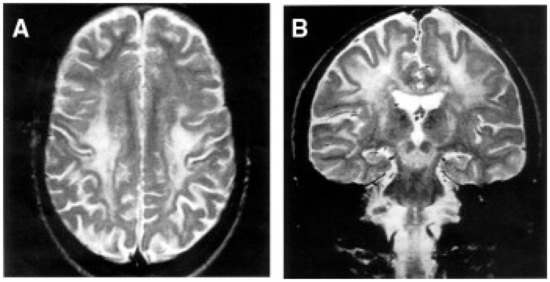

- Barkovich, A.J.; Good, W.V.; Koch, T.K.; Berg, B.O. Mitochondrial Disorders: Analysis of Their Clinical and Imaging Characteristics. AJNR Am. J. Neuroradiol. 1993, 14, 1119–1137. [Google Scholar] [PubMed]

- Oldfors, A.; Fyhr, I.M.; Holme, E.; Larsson, N.G.; Tulinius, M. Neuropathology in Kearns-Sayre Syndrome. Acta Neuropathol. 1990, 80, 541–546. [Google Scholar] [CrossRef]

- McKelvie, P.A.; Morley, J.B.; Byrne, E.; Marzuki, S. Mitochondrial Encephalomyopathies: A Correlation between Neuropathological Findings and Defects in Mitochondrial DNA. J. Neurol. Sci. 1991, 102, 51–60. [Google Scholar] [CrossRef]

- Tanji, K.; Vu, T.H.; Schon, E.A.; DiMauro, S.; Bonilla, E. Kearns-Sayre Syndrome: Unusual Pattern of Expression of Subunits of the Respiratory Chain in the Cerebellar System. Ann. Neurol. 1999, 45, 377–383. [Google Scholar] [CrossRef]